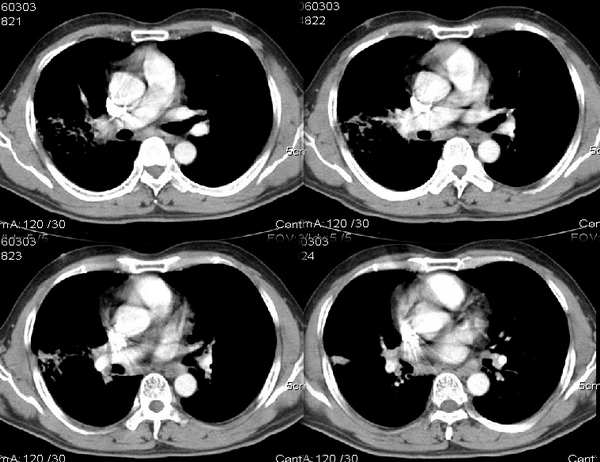

男54岁咳嗽咯痰2w,外院胸片示“右上大叶性肺炎抗炎治疗后部分吸收

结合病史,右上肺病变考虑炎症,继续抗炎治疗后复查;

该病人54岁,胸膜下可见多个类圆形透亮影,是不是还要考虑慢性/弥漫性肺疾病可能?

请问右中叶支气管开口旁不强化结节影是什么?

炎症吸收期,请继续抗炎治疗后复查或行纤维支气管镜活检。

可以考虑外院诊断:右上肺大叶性肺炎吸收期改变。

右上叶支气管变窄.ca?